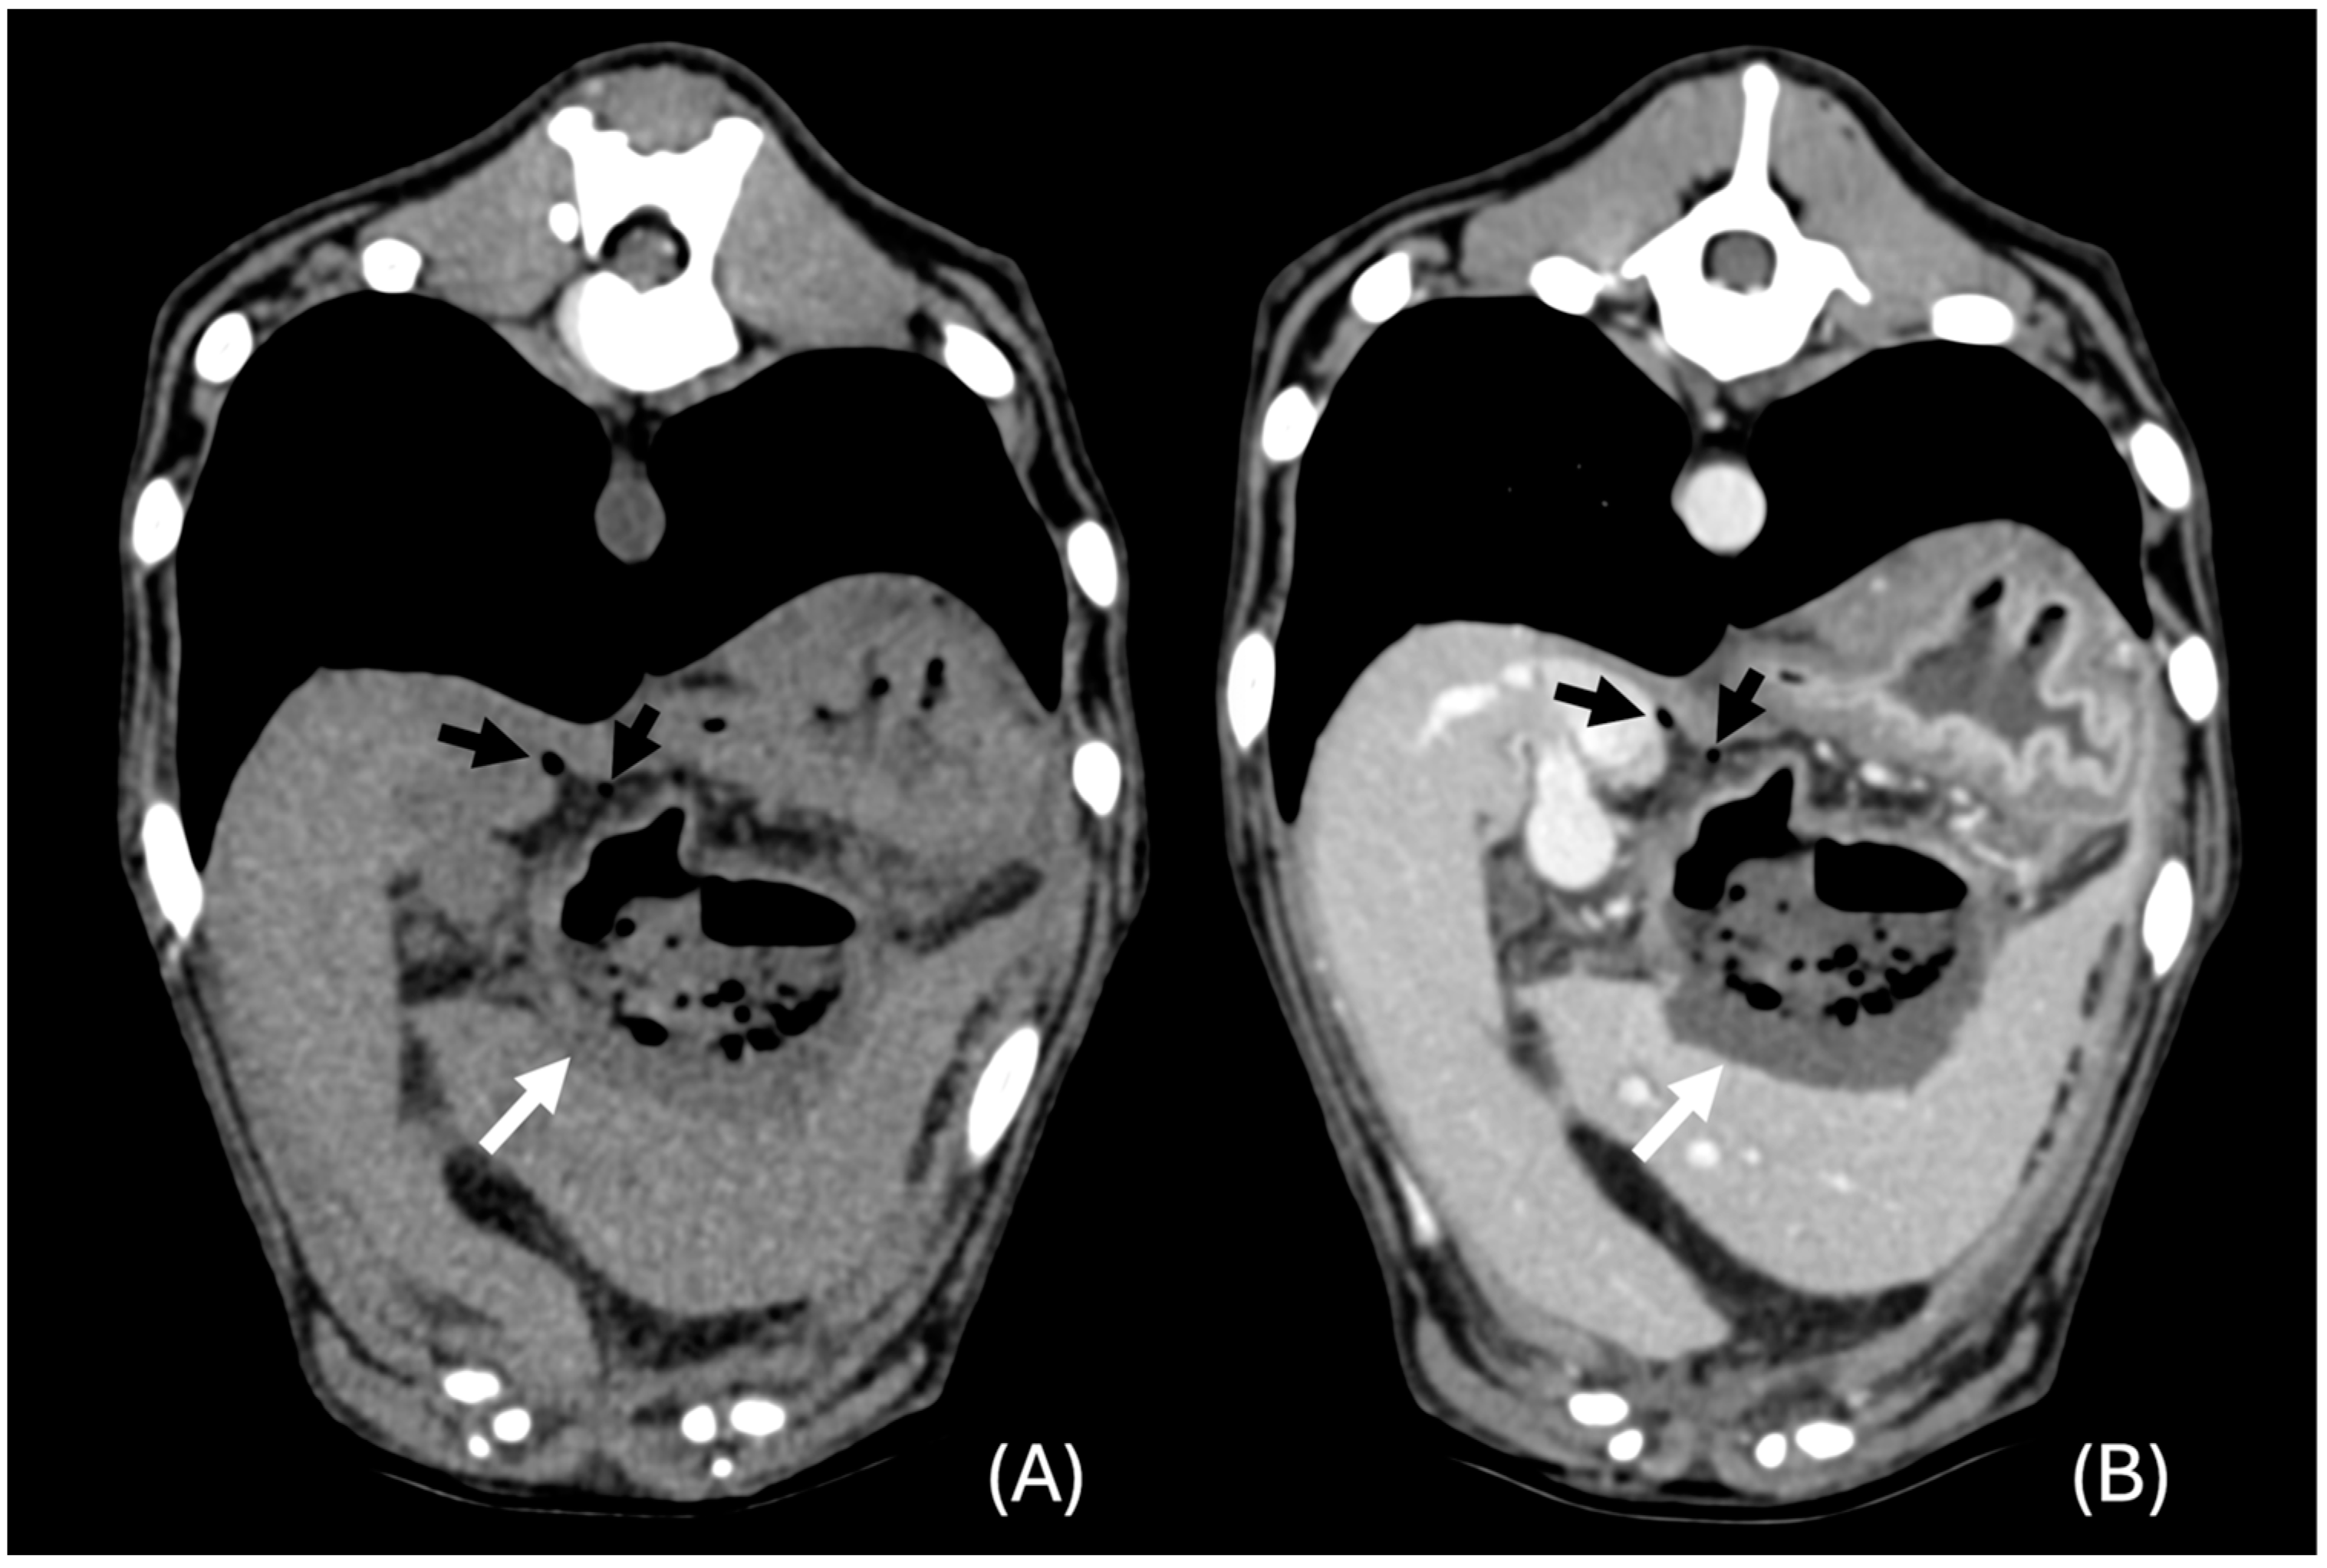

3.6.1. “Diffuse” Changes

3.6.2. “Discrete” Changes